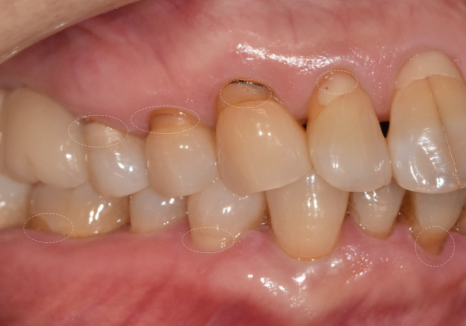

입안을 직접 살펴보니

굳이 말씀을 안 하셔도...

평소 식습관을 알 수 있을 정도였는데요~

치아의 씹는 면이

맷돌처럼 평평하게 마모되어 있었고

군데군데 작게 깨진 흔적들도 많았거든요.

251229

특히 치아와 잇몸이 만나는 목 부위가

도끼로 찍은 듯 파여있는

치경부 마모 증상도 관찰되었습니다.

강한 힘으로 음식을 씹을 때

치아가 미세하게 휘어지면서

가장 약한 목 부분이 떨어져 나가는 현상이죠.

이는 딱딱한 음식을 즐기는 분들에게

흔히 나타나는 징후들입니다.